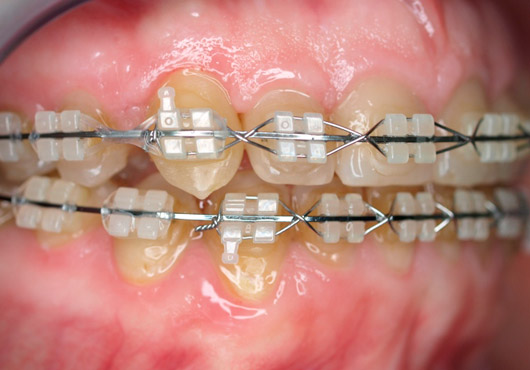

En Indenta ofrecemos tratamientos que adaptamos a las necesidades de cada Paciente y que compaginan técnicas tradicionales, como la Ortodoncia Vestibular, la mas efectiva a lo largo del tiempo, mediante Brackets Metálicos o Brackets Estéticos transparentes o apenas visibles , de cerámica, con tratamientos basados en las técnicas más modernas y novedosas como el “Invisaling” que se realiza aplicando férulas de plásticos termoformados, casi invisibles.

CASO 1: expansión+extrusión de caninos y colocación de los mismos en el lugar adecuado.

CASO 2: extrusión y colocacion del canino superior derecho retenido en el paladar, y corrección del resto de los dientes.

CASO 3: apiñamiento y falta de tamaño maxilar corregido

CASO 4: corrección de apiñamiento y crear espacio para colocar 2 implantes a nivel de 5+5 por agenesia de los mismos.

CASO 5: solución ortodóntica tras realizar la frenectomía para alinear y ocluir los dientes.